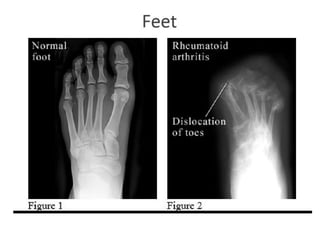

•X-ray- joint narrowing, erosions at the joint

margins